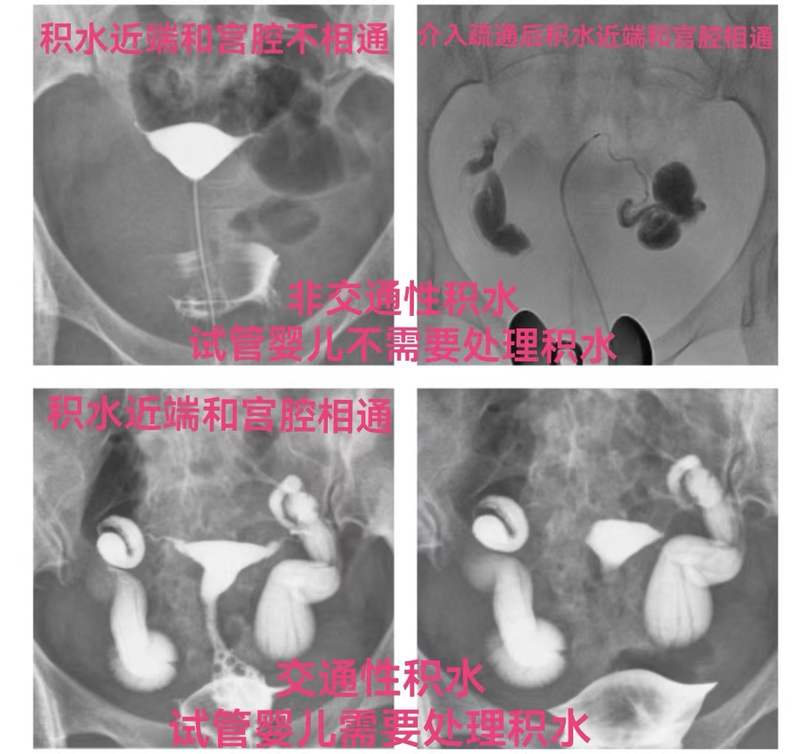

双侧输卵管积水者一般不能自然怀孕,积水的输卵管功能良好者常需腹腔镜行输卵管积水远端造口术后才能自然怀孕,或通过试管婴儿来助孕。研究显示输卵管积水降低了IVF-ET约50%胚胎着床率及妊娠率,并且增加1倍流产率,增加了异位妊娠的发生率。目前国内外生殖医学专家已达成共识:为提高试管婴儿的成功率,在试管婴儿的胚胎移植前需要处理输卵管积水。目前,处理输卵管积水的方法主要有5种:1、腹腔镜输卵管近段结扎并积水远端造口术;2、输卵管积水近段介入栓塞术。3、输卵管切除术;4、输卵管积水远端造口术;5、超引导下输卵管积水抽吸术。 目前在国内处理输卵管积水的方法主要有两种:1、腹腔镜输卵管近段结扎并积水远端造口术;2、输卵管积水近段介入栓塞术。一般最好是做腹腔镜行近段结扎并积水远端造口术。因为手术不仅成功率极高(在99%以上),而且还同时可以对输卵管远端造口术等盆腔情况进行全面诊疗。只有对严重盆腔粘连不能手术者或者不愿意手术者才进行输卵管近段介入栓塞术。 输卵管积水按输卵管近段是否与子宫腔相通分为2类:1、近段与子宫腔相通的交通性输卵管积水,约90%,胚胎移植前输卵管积水需要做处理;2、近段与子宫腔不相通的非交通性输卵管积水,约10%,胚胎移植前输卵管积水不需要做处理。 典型的输卵管积水比较容易诊断,影像表现主要2点:1、造影相输卵管壶腹部和/或伞部扩张,造影剂呈团片聚集,伞端未见造影剂溢出至盆腔。2、弥散相输卵管壶腹部和/或伞部见造影剂残留影,盆腔未见造影剂弥散影。 不典型输卵管积水常常被误诊为输卵管通而不畅。不典型输卵管积水影像表现为造影相输卵管壶腹部和伞部扩张,造影剂呈团片聚集,伞端未见或可见少许造影剂溢出至盆腔。弥散相输卵管壶腹部和伞部见造影剂残留影,盆腔见少量造影剂弥散影。伞端可见少许造影剂溢出至盆腔是因为随着造影剂进入输卵管增多,输卵管内压力增高,粘连闭锁的伞端被冲破出出一个裂缝,造影剂从伞部裂缝溢出至盆腔。积水腹腔镜造口术复发率比较高,伞部仅仅一个裂缝会很快就复粘,积水很快就会复发。对宫腔的胚胎同样有不利影响。 不典型输卵管积水也是输卵管积水,也是能降低了试管婴儿约50%胚胎着床率及妊娠率,并且增加1倍流产率,增加了异位妊娠的发生率。同样应该在胚胎移植前处理输卵管积水,以提试管婴儿的成功率。 为了提高大家对不典型输卵管积水的诊断水平,2020年我专门录制有关输卵管造影和输卵管介入诊疗11节课,其中第四节输卵管堵塞和积水的子宫输卵管造影,在第六部分就专门讲不典型输卵管积水的影像表现,其中拿出4个腹腔镜手术证实的不典型双侧输卵管积水的子宫输卵管造影片进行图片分析和解读。下面是第4例的造影片和出院记录。 2024年7月8日有一位云南省昆明市的赵女士从好大夫在线联系我,到我们科做子宫输卵管造影。赵女士做造影时,我就去看,诊断她不典型右侧输卵管轻度积水。随后有事就外出了,就微信同她讲“您拿到报告单和胶片后等下,我一会上去同您讲解。”等到我再回到科室后发现造影报告诊断输卵管通而不畅,就立即语音同她讲,让她上来。她说她在一楼,一会就上来。8分钟她还没有上来,我又语音她,她没接。微信给她留言,也没回。考虑到她是轻度积水,积水反流宫腔不是很多。又担心,告诉她输卵管积水,她有可能会紧张。对以后的治疗也不好。就没有再联系她。赵女士最近2024年6月19日和6月24日,二次超声都发现右侧输卵管积水;子宫输卵管造影(HSG)显示右侧不典型输卵管积水,就可以明确右侧输卵管积水。祝她早日好孕! 总之,不管是典型输卵管积水,还是不典型输卵管积水,都应该在试管婴儿的胚胎移植前处理输卵管积水,以提高试管婴儿的成功率,降低流产几率,最终提高抱婴率。

中外生殖医学专家早就达成共识:在移植胚胎前需要处理输卵管积水,以提高试管婴儿的成功率。试管前是否有不需要处理的输卵管积水?答案是有的,可分为2种情况:一种是非交通性输卵管积水,另一种是误诊的输卵管积水。输卵管积水按近端是否和宫腔相通分为近端与宫腔相通的交通性输卵管积水和近端与宫腔不相通的非交通性输卵管积水2种。 (1)、近端与子宫腔相通交通性输卵管积水,约占85%左右,造影和超声均可以显示;这种积水可以倒流进入宫腔,对宫腔的胚胎有影响,在胚胎移植前需处理积水。(2)、近端与子宫腔不相通的非交通性输卵管积水,约占15%左右,造影因输卵管近端堵塞,造影剂不能进入输卵管显示不了输卵管积水,超声可以显示积水。这种积水因输卵管近端堵塞不可以倒流进入宫腔,对宫腔的胚胎没有影响,在胚胎移植前不需处理积水。 下面是一例误诊为输卵管积水者。2018年我在大医汇准备给一位江西的女士做输卵管积水近段介入栓塞术。邱XX,女,32岁,江西省赣州人,家里是做生意的,生活富足,开放2胎后想儿女双全。在江西省赣州市做超声提示双侧输卵管积水,就在胚胎移植前想找我做双侧输卵管积水近段栓塞术。我在给她做栓塞术前做造影时发现她双侧输卵管没有积水,大致是通畅的。原来超声发现的不是输卵管积水,应该是输卵管系膜囊肿。就没有给她做栓塞术,就做个子宫输卵管造影就结束了。下面是她在好大夫在线发给我的感谢信。 经验:对于做试管婴儿超声诊断输卵管积水者,最好做一个子宫输卵管造影明确一下是否是输卵管积水,或者积水是否和宫腔相通,在胚胎移植前是否需要处理积水。尽量帮助她们经历最少的痛苦,以最低的代价,取得最佳的效果。